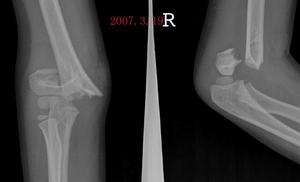

X線檢查的特徵是受傷後不久可出現局限性腫快。傷後3~4周,在腫快內顯示毛狀緻密象,其臨近骨將顯示骨膜反應。傷後6~8周,病變邊緣部清楚地被緻密骨質所包繞,而具有新生骨的外貌。軟組織腫塊的核心部有時顯囊性變且逐漸擴大其內腔,到晚期而顯出類似蛋殼狀的囊腫。傷後5~6個月腫塊收縮,因而腫塊與鄰近的骨皮質和骨膜反應之間顯出X線透亮帶。